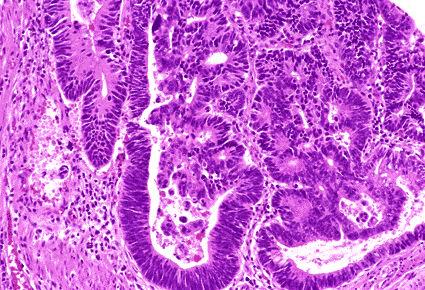

Cancer of the ascending colon. Well differentiated adenocarcinoma. Cellular atypism and structural atypism of the gland are observed.

악성 상피성종양/선암